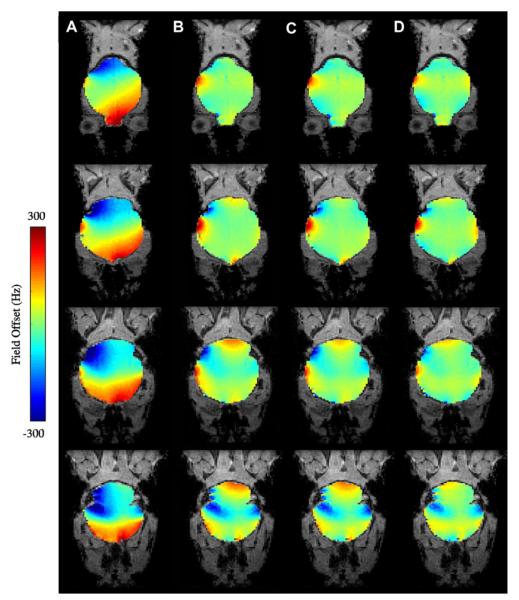

(A) Axial MRI at B0 = 3T of two axial slices encompassing the sinus cavity region, residual inhomogeneity after (B) first order shimming, (C) with the inclusion of second-order shims, (D) with the inclusion of third-order shims.

Fig. 9 similarly shows residual field maps after global shimming of the mouse brain at 9.4T. The residual inhomogeneity here is even more severe than in the human case due to (a) the higher magnetic field strengths of small-animal MR systems and (b) the more complicated air-cavity distributions in the mouse head. Viable high-field, whole-brain, single-shot EPI images of the mouse brain have yet to be demonstrated because of this residual inhomogeneity. This severely limits the quality and temporal resolution of BOLD and DTI studies on the mouse brain.

Fig. 9.

Coronal field inhomogeneity maps of the mouse brain at 9.4T with (A) no shimming, (B) first-order shimming, (C) first and second-order shimming, and (D) first through third-order shimming.